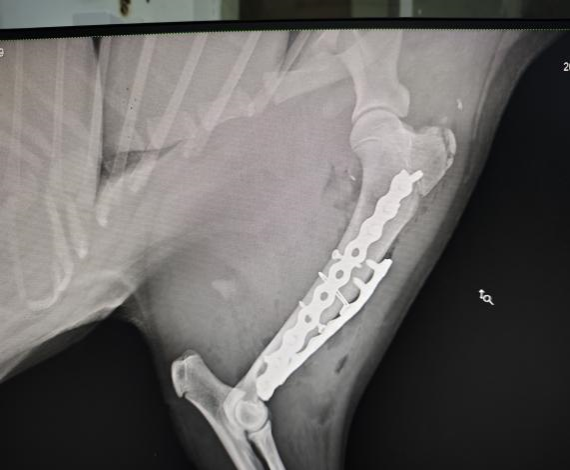

手术后左前肢侧位X光

手术团队由德赢VWIN官方网站教学动物医院院长沈留红、动物外科专家石先鹏、动物内科专家巫晓峰、医生陈善瑜和罗皓、麻醉医生邓聪辉、手术助手王郡东、助理唐清婷、张涵艺、钱琳、王均、李鑫等组成,并与动物园动物疾病预防组刘俊卿副经理团队一道组成会诊专家组,确定麻醉和手术方案。外科专家石先鹏凭借丰富的经验和精湛的技术,对水豚肱骨进行了精确的复位和固定。手术全程在严格的无菌条件下进行,确保了安全性和成功率。